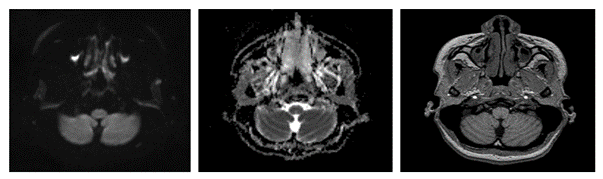

Imagen 1. D y E) RM del cerebro en plano axial, en secuencia T1, TRACE y ADC donde no se observa restricción a la difusión. F) RM del cerebro en el plano axial, secuencia T1 post contraste donde no se observa realce de la lesión descrita.